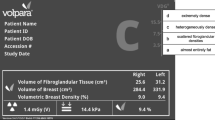

BI-RADS breast density and dense breast volume

Practicing radiologists classified breast density as part of routine clinical practice at the time of mammography interpretation using the BI-RADS® density categories [2]: a = almost entirely fat, b = scattered fibroglandular densities, c = heterogeneously dense, and d = extremely dense. Volpara™ version 1.5.0, which is the most common automated 3D density measurement tool used in clinical practice and research settings, is a fully automated method for assessing volumetric breast density that uses the measured breast thickness and X-ray attenuations in the “for processing” image to create estimates of dense and nondense tissue volume for each pixel. Summing the dense pixel volumes provides total dense breast volume. Volpara uses proprietary algorithms to calculate breast thickness and determine dense tissue volume [15] by averaging measures of each breast. For this study, we used the dense breast volume output from the vendor-specific software per woman, incorporating all four views (craniocaudal and mediolateral oblique of both breasts) of raw digital images as done in the clinical setting.